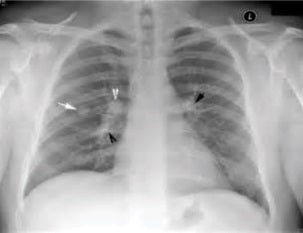

Pulmonary Nodules: What are They and Should You Worry?

Pulmonary nodules—or spots on the lung—are the source of...